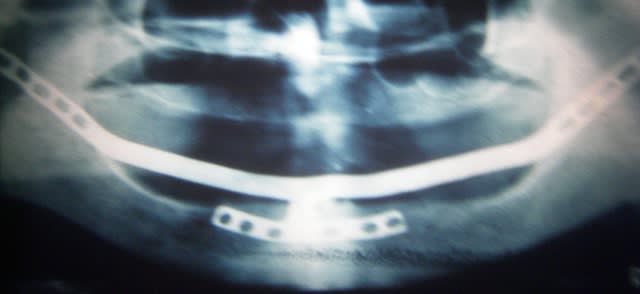

En voilà un qui a 21 ans.

sauf erreur mon cher Olivier, tu t'es trompé (je savais que je l'aurais) tu nous montre un fort beau cas, sauf erreur de ma part, de sous périosté (j'ai commencé par ça en 84) or je montre un cadre ramique qui est implanté dans la symphise et dans les deux branches ramiques

Effectivement mea culpa, il s'agit d'un sous periosté avec appui symphysaire et ramique bilatéral.

Comme quoi, à cette époque, l'implantologie, c'était vraiment du grand art chirurgical !! (sans ironie) Chapeau pxav ! Oser faire des tranchées comme celles là dans les branches montantes, il fallait en avoir des "cojones" !!